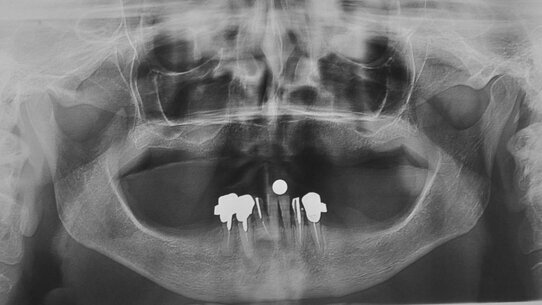

La paziente di anni 54, non fumatrice, non è affetta da patologie sistemiche e presenta un buono standard di igiene orale. Da circa 20 anni è edentula nei settori diatorici mandibolari. La documentazione radiografica evidenzia notevole atrofia mandibolare nei settori posteriori. Gli esami OPT e TC dental scan analizzati, esprimono un’altezza ossea massima in regione 36 di 7 mm e in regione 46 di 6,5 mm. Le procedure di rigenerazione ossea preimplantare proposte alla paziente vengono rifiutate. Vengono rilevate impronte in alginato e cera di masticazione, al fine di eseguire ceratura diagnostica e mascherina chirurgica. La ceratura diagnostica eseguita esprime un corretto rapporto intermascellare e un risultato protesico, valido sia ai fini funzionali che estetici. La paziente viene sottoposta a seduta di igiene orale una settimana prima dell’intervento. La profilassi antibiotica ha previsto l’assunzione di amoxicillina 0,875 mg + acido clavulanico 0,125 1 cps ogni 12 ore a partire dalla mattina del giorno precedente l’intervento e da sciacqui con clorexidina collutorio allo 0,2% praticati per 1 minuto poco prima dell’inizio dell’intervento. La paziente pertanto viene sottoposta a bonifica totale dell’arcata inferiore e a contestuale inserimento di 6 impianti dentali Geass, dei quali 4 way Milano di lunghezza 11 e diametro 4,5, in regione intrasinfisaria. I restanti 2 impianti dentali Geass short – lunghezza 6,5, diametro 4,5, piattaforma 4,8 – vengono inseriti in regione 36 e 46. Il torque di inserimento implantare va dai 40 ai 50 Ncm. Si rilevano impronte di precisione utilizzando transfert rotazionali solidarizzati con pattern fotopolimerizzabile e portaimpronte individuali. Il materiale da impronta usato è il polietere con tecnica monofase. Si inseriscono viti di guarigione sui 6 impianti e si pratica terapia farmacologica antinfiammatoria (desametasone 1 fl da 4 mg). Viene eseguita Rx opt postoperatoria che evidenzia il corretto inserimento implantare. La paziente viene dimessa con terapia farmacologica domiciliare: antibiotica sistemica e locale (clorexidina coll. 0,2% e gel), antidolorifica (naporossene) e gastroprotettiva (esomeprazolo). A 48 ore, la paziente viene sottoposta al carico protesico immediato avvitato. La protesi provvisoria è realizzata in resina rinforzata con fibra di vetro. Il lavoro protesico viene avvitato agli impianti con torque di 20 Ncm. Si verifica l’occlusione del manufatto protesico. Il controllo clinico a 2, 7 e 21 giorni evidenzia una buona guarigione dei tessuti.